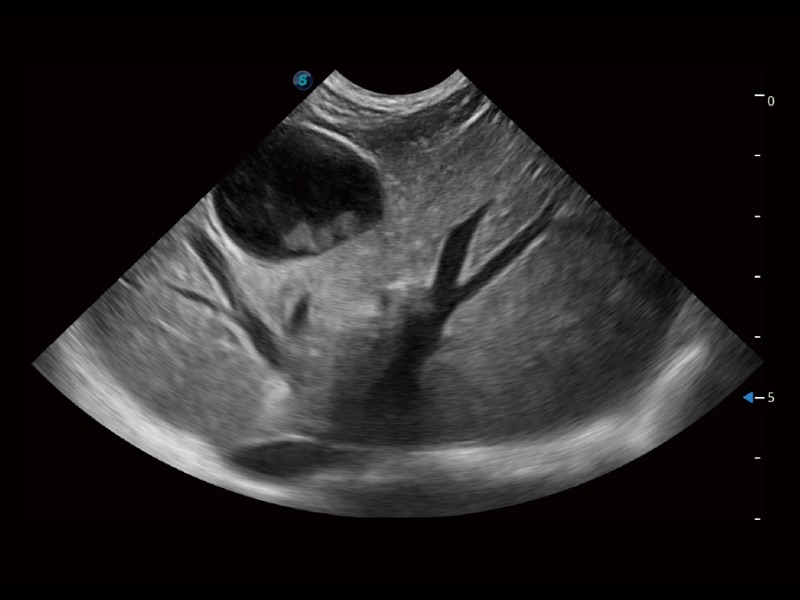

(犬)胎儿主动脉弓立体血流